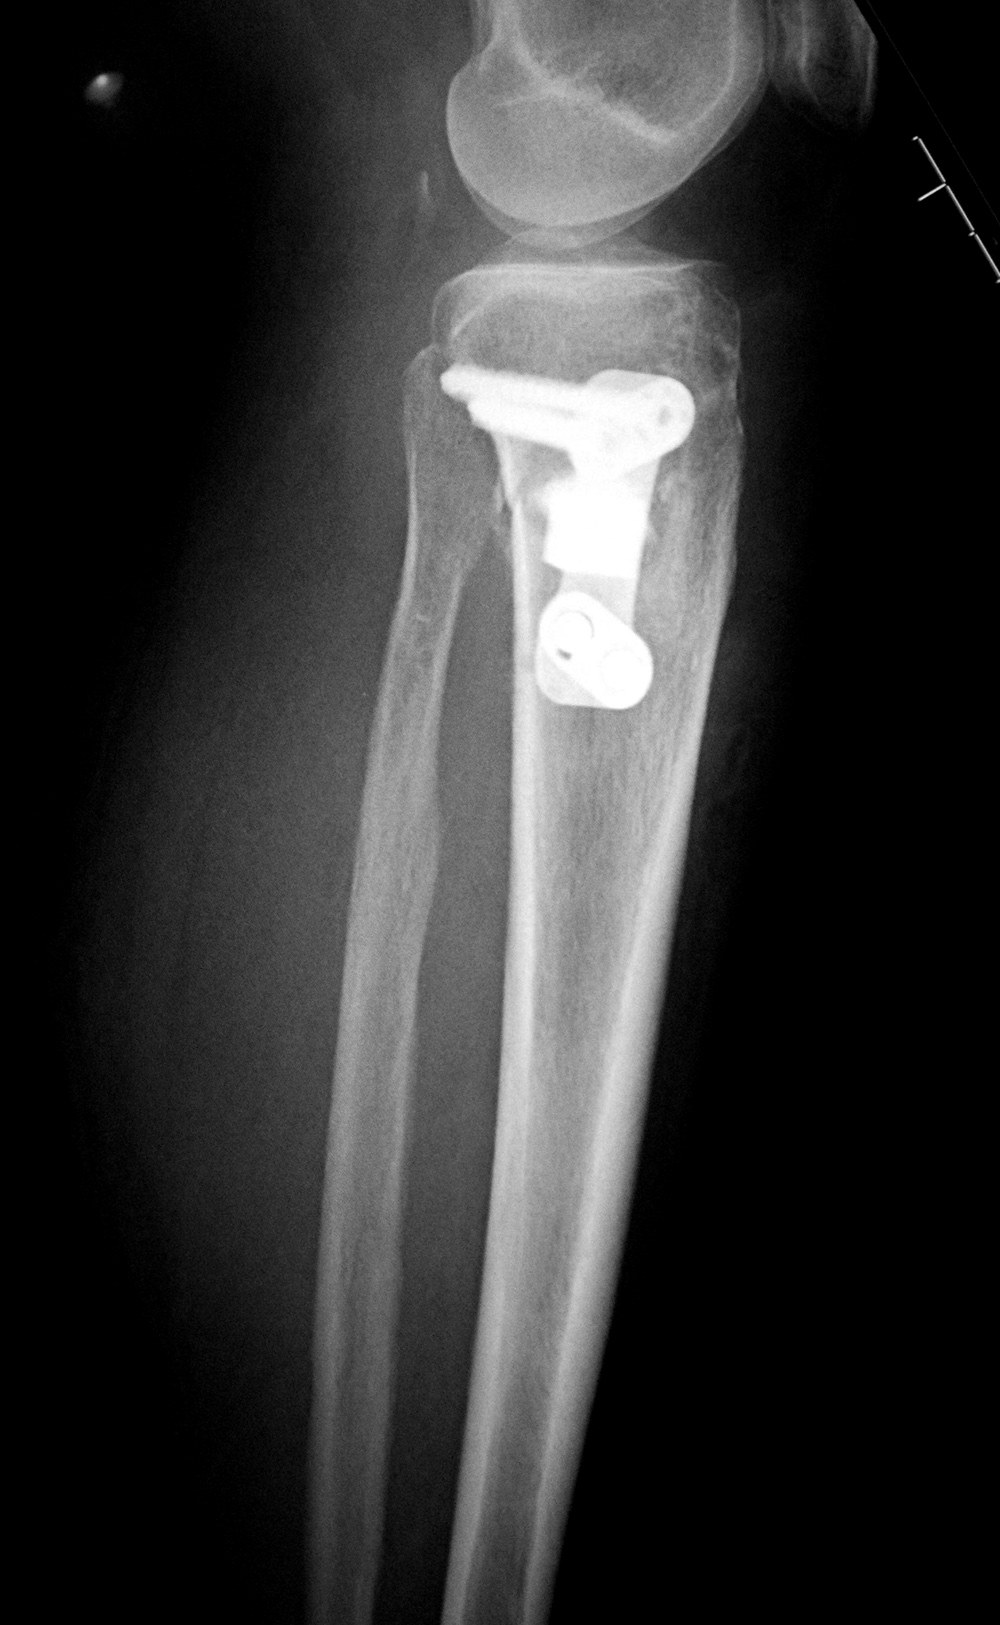

Right tibia bone graft

43 year-old man with comminuted right tibia and fibula fractures as well as extensive bone loss and soft tissue injury. A tibial intramedullary nail with proximal and distal locking screws is present as well as multiple rounded bony allografts. There are also large skin staples.